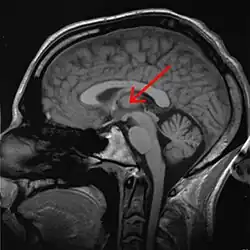

Tálamo (anatomia)

O tálamo é uma estrutura localizada no diencéfalo, entre o córtex cerebral e o mesencéfalo, formada fundamentalmente por substância cinzenta (núcleos de neurônios) do encéfalo [1]. São duas massas neuronais situadas na profundidade dos hemisférios cerebrais. Dentre suas funções estão a transmissão de sinais motores e sensitivos para o córtex [2], além da regulação da consciência, sono e estado de alerta.

O tálamo é um conjunto bem definido de vários núcleos de neurônios e forma uma parte maior do diencéfalo. Existem dois deles situados em posições simétricas, à esquerda e à direita, cada um covixem cerca de 1 cm de comprimento. Sua extremidade anterior é estreita e arredondada, e constitui a parede posterior do forame interventricular; a porção posterior é expandida e está acima do colículo superior; a superfície inferior situa-se continuamente ao tegmento do mesencéfalo; sua face medial está confrontada com a mesma do outro tálamo e contém uma região de comunicação com ele, a adesão intertalâmica, que está rodeada pelo terceiro ventrículo.